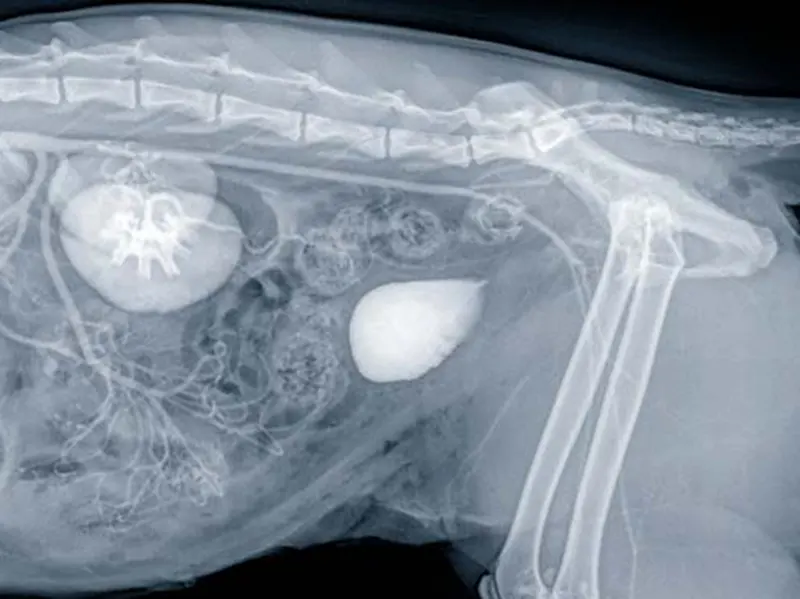

Rendgenske snimke su neinvazivan način za uvid u nutrinu naših ljubimaca.

Dvije glavne vrste tkiva u koje dobivamo uvid pomoću rendgenskog snimanja su kosti i strukture mekog tkiva.

Pomoću rendgena, između ostaloga, možemo dijagnosticirati:

Rendgenskim pregledima se također mogu pratiti zarastanja prijeloma, promatranje uspješnosti ortopedskih operacija ili rast kostiju kod mladih životinja.